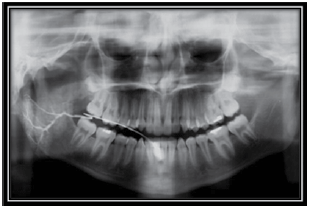

Observe a figura a seguir e responda à questão.

O exame contrastado representado na figura é o de